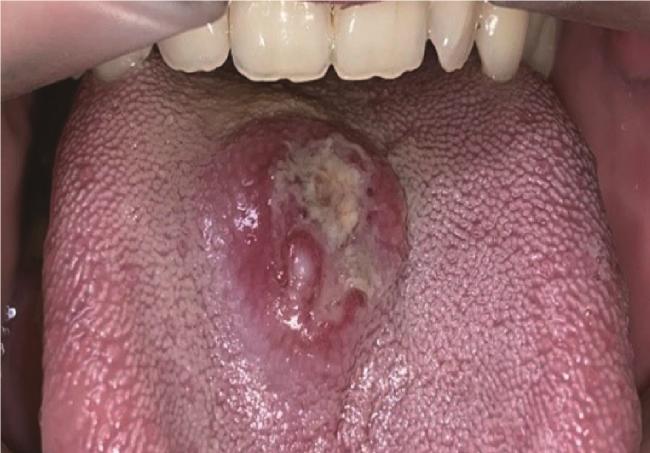

2.1 典型病例1

病例1为男性,30岁,主因“发现舌背肿物1周”就诊。患者就诊一周前疑似进食不洁食物后舌背出现肿物,初为黄豆大小,自觉异物感,后肿物迅速增大,表面出现白色假膜,可自行揭开,少量出血后可自止,伴轻度疼痛,未行诊治。自述既往进食不洁食物后四肢曾出现红疹;既往淋病史。否认食物和药物过敏史。专科检查:舌背正中偏右可见一直径2 cm类圆形溃疡,隆起于黏膜,溃疡表面有白色假膜覆盖,不均匀,溃疡周围黏膜充血水肿。扪诊溃疡基底有硬结,轻度触痛(图 1)。头颈部CT示舌背正中类圆形软组织肿物影,边界较清楚,轻度强化(图 2)。实验室检查:白细胞计数10.21×109/L(正常值为3.5×109/L~9.5×109/L);中性粒细胞比例50.6%(正常值40%~75%);中性粒细胞绝对值5.17×109/L(正常值1.8×109/L~6.3×109/L);嗜酸粒细胞比例16.3%(正常值0.4%~8.0%);嗜酸粒细胞绝对值1.66×109/L(正常值0.02×109/L~0.52×109/L)。血清IgE为5.1 IU/mL(正常 < 100 IU/mL)。唾液涂片镜检可见革兰阳性球菌、革兰阴性杆菌,未见念珠菌菌丝。临床初步诊断为舌背肿物。

图1 病例1,舌背黏膜溃疡,表面覆盖假膜,周缘隆起

Figure 1 Case 1, an ulcer on the dorsum of the tongue, which is covered with pseudomembrane and surrounded by elevated lesion